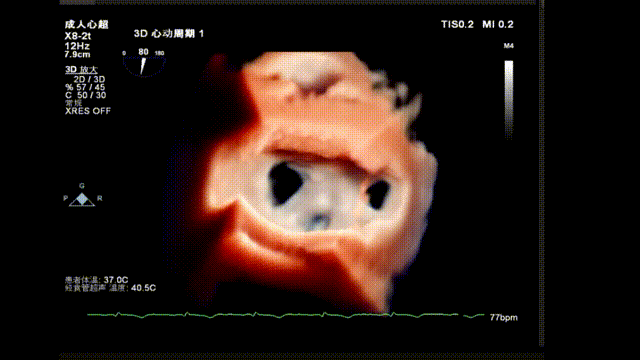

术前TEE显示重度功能性二尖瓣反流,反流位于A2/P2